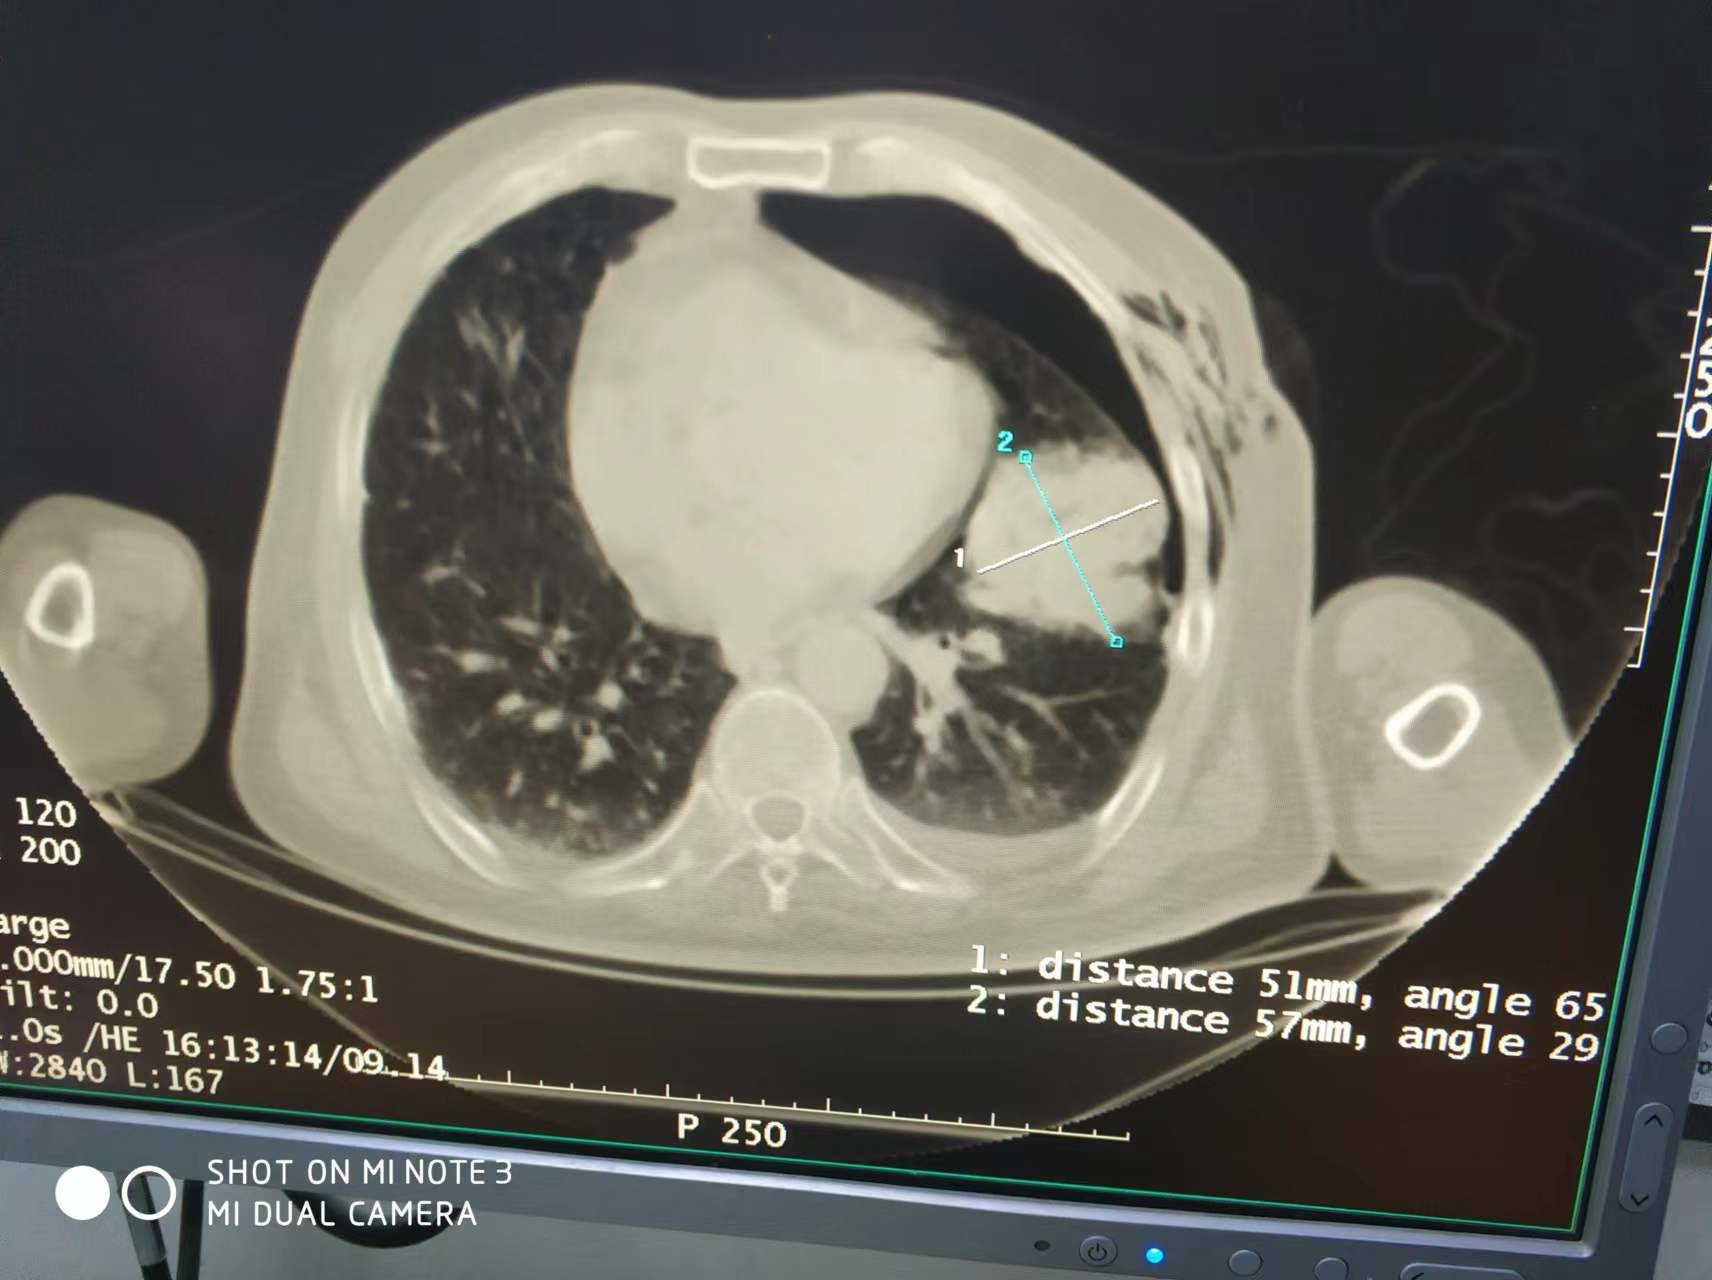

上一篇:2022年4月份肺部氩氦刀手术